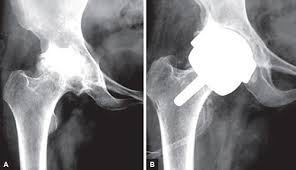

이 때에는 ‘인공관절 치환술’이 유일한 해결책으로 지목된다고 한다. 망가진 관절 대신, 그 자리에 새로운 관절을 이식하는 것이 바로 ‘인공관절 치환술’이라고 한다.

인공관절 수술은 원리에 따라 다양하게 나뉘며 닳아 없어진 무릎 연골 대신 인체에 해가 없는 코발트크롬, 티타늄합금 등의 금속이나 세라믹으로 만들어진 인공관절을 삽입하는 과정으로 진행된다고 한다. 다만 환자 입장에선 자신에게 적합한 수술법을 찾는 것이 더욱 중요해졌다고 한다.

완성된 출력물 즉, 관절 절삭 부위를 알려주는 ‘PSI(Patient Specific Instrument)’라는 절삭유도장치라고 한다. 수술 시 손상된 관절 부위에 PSI를 끼우고 망가진 관절을 잘라내면 인공관절이 정확한 자리에 이식된다고 한다.